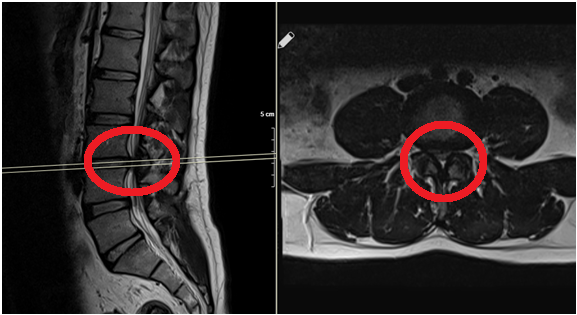

Omurga enfeksiyonları, omurga kemiklerini (vertebra), omurlar arasındaki diskleri veya omuriliği çevreleyen dokuları etkileyen ciddi bir enfeksiyon türüdür. Bu durum, genellikle bakteriyel veya fungal enfeksiyonlardan kaynaklanır ve erken teşhis edilmediği takdirde...